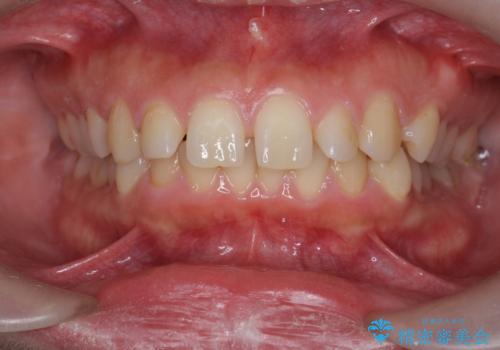

深い噛み合わせ、すきっ歯の改善 ワイヤーを用いたマルチブラケット矯正

- 噛み合わせが深く、前歯が突き出て隙間が出てきたことの改善を希望され矯正治療の相談で当院に初診来院されました。

ワイヤーを用いたマルチブラケット矯正を行うことで深い噛み合わせを改善し、前歯の隙間もなくし審美的な歯列へと治療をおこなっていきます。